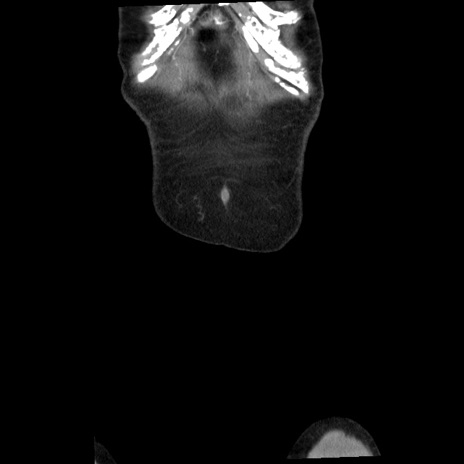

症例1(冠状断像)

【症例】80歳代女性

【主訴】腹痛

【現病歴】8時間前から腹痛あり来院。

【既往歴】糖尿病、脂質異常症、子宮体癌にて子宮全摘術

【身体所見】意識清明・会話良好だが腹痛で苦悶様、全腹部にわたって反跳痛と圧痛あり

【データ】WBC 13600、CRP 0.14、LDH 224、CK 90